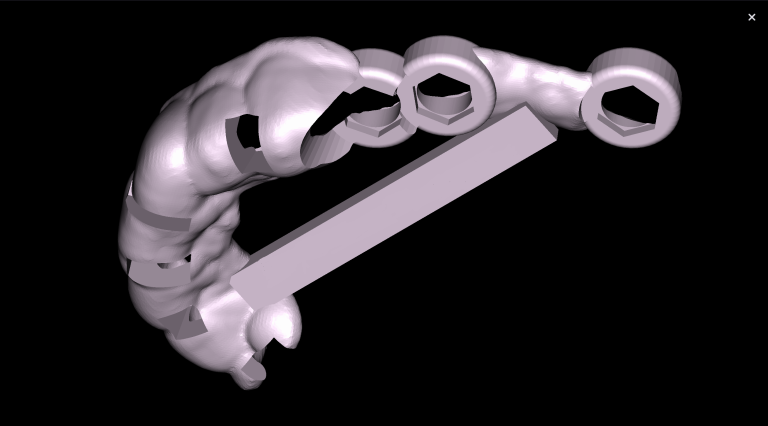

The “STL” module enables the creation of virtual models for guided implant surgery. This is achieved by loading intraoral scan data into the module and selecting a suitable CBCT for merging

The slide illustrates the sequence of stages involved in prosthetic rehabilitation, obtaining digital impressions and uploading them to the Diagnocat STL module, to creating temporary crowns and forming the desired emergence profiles for implants